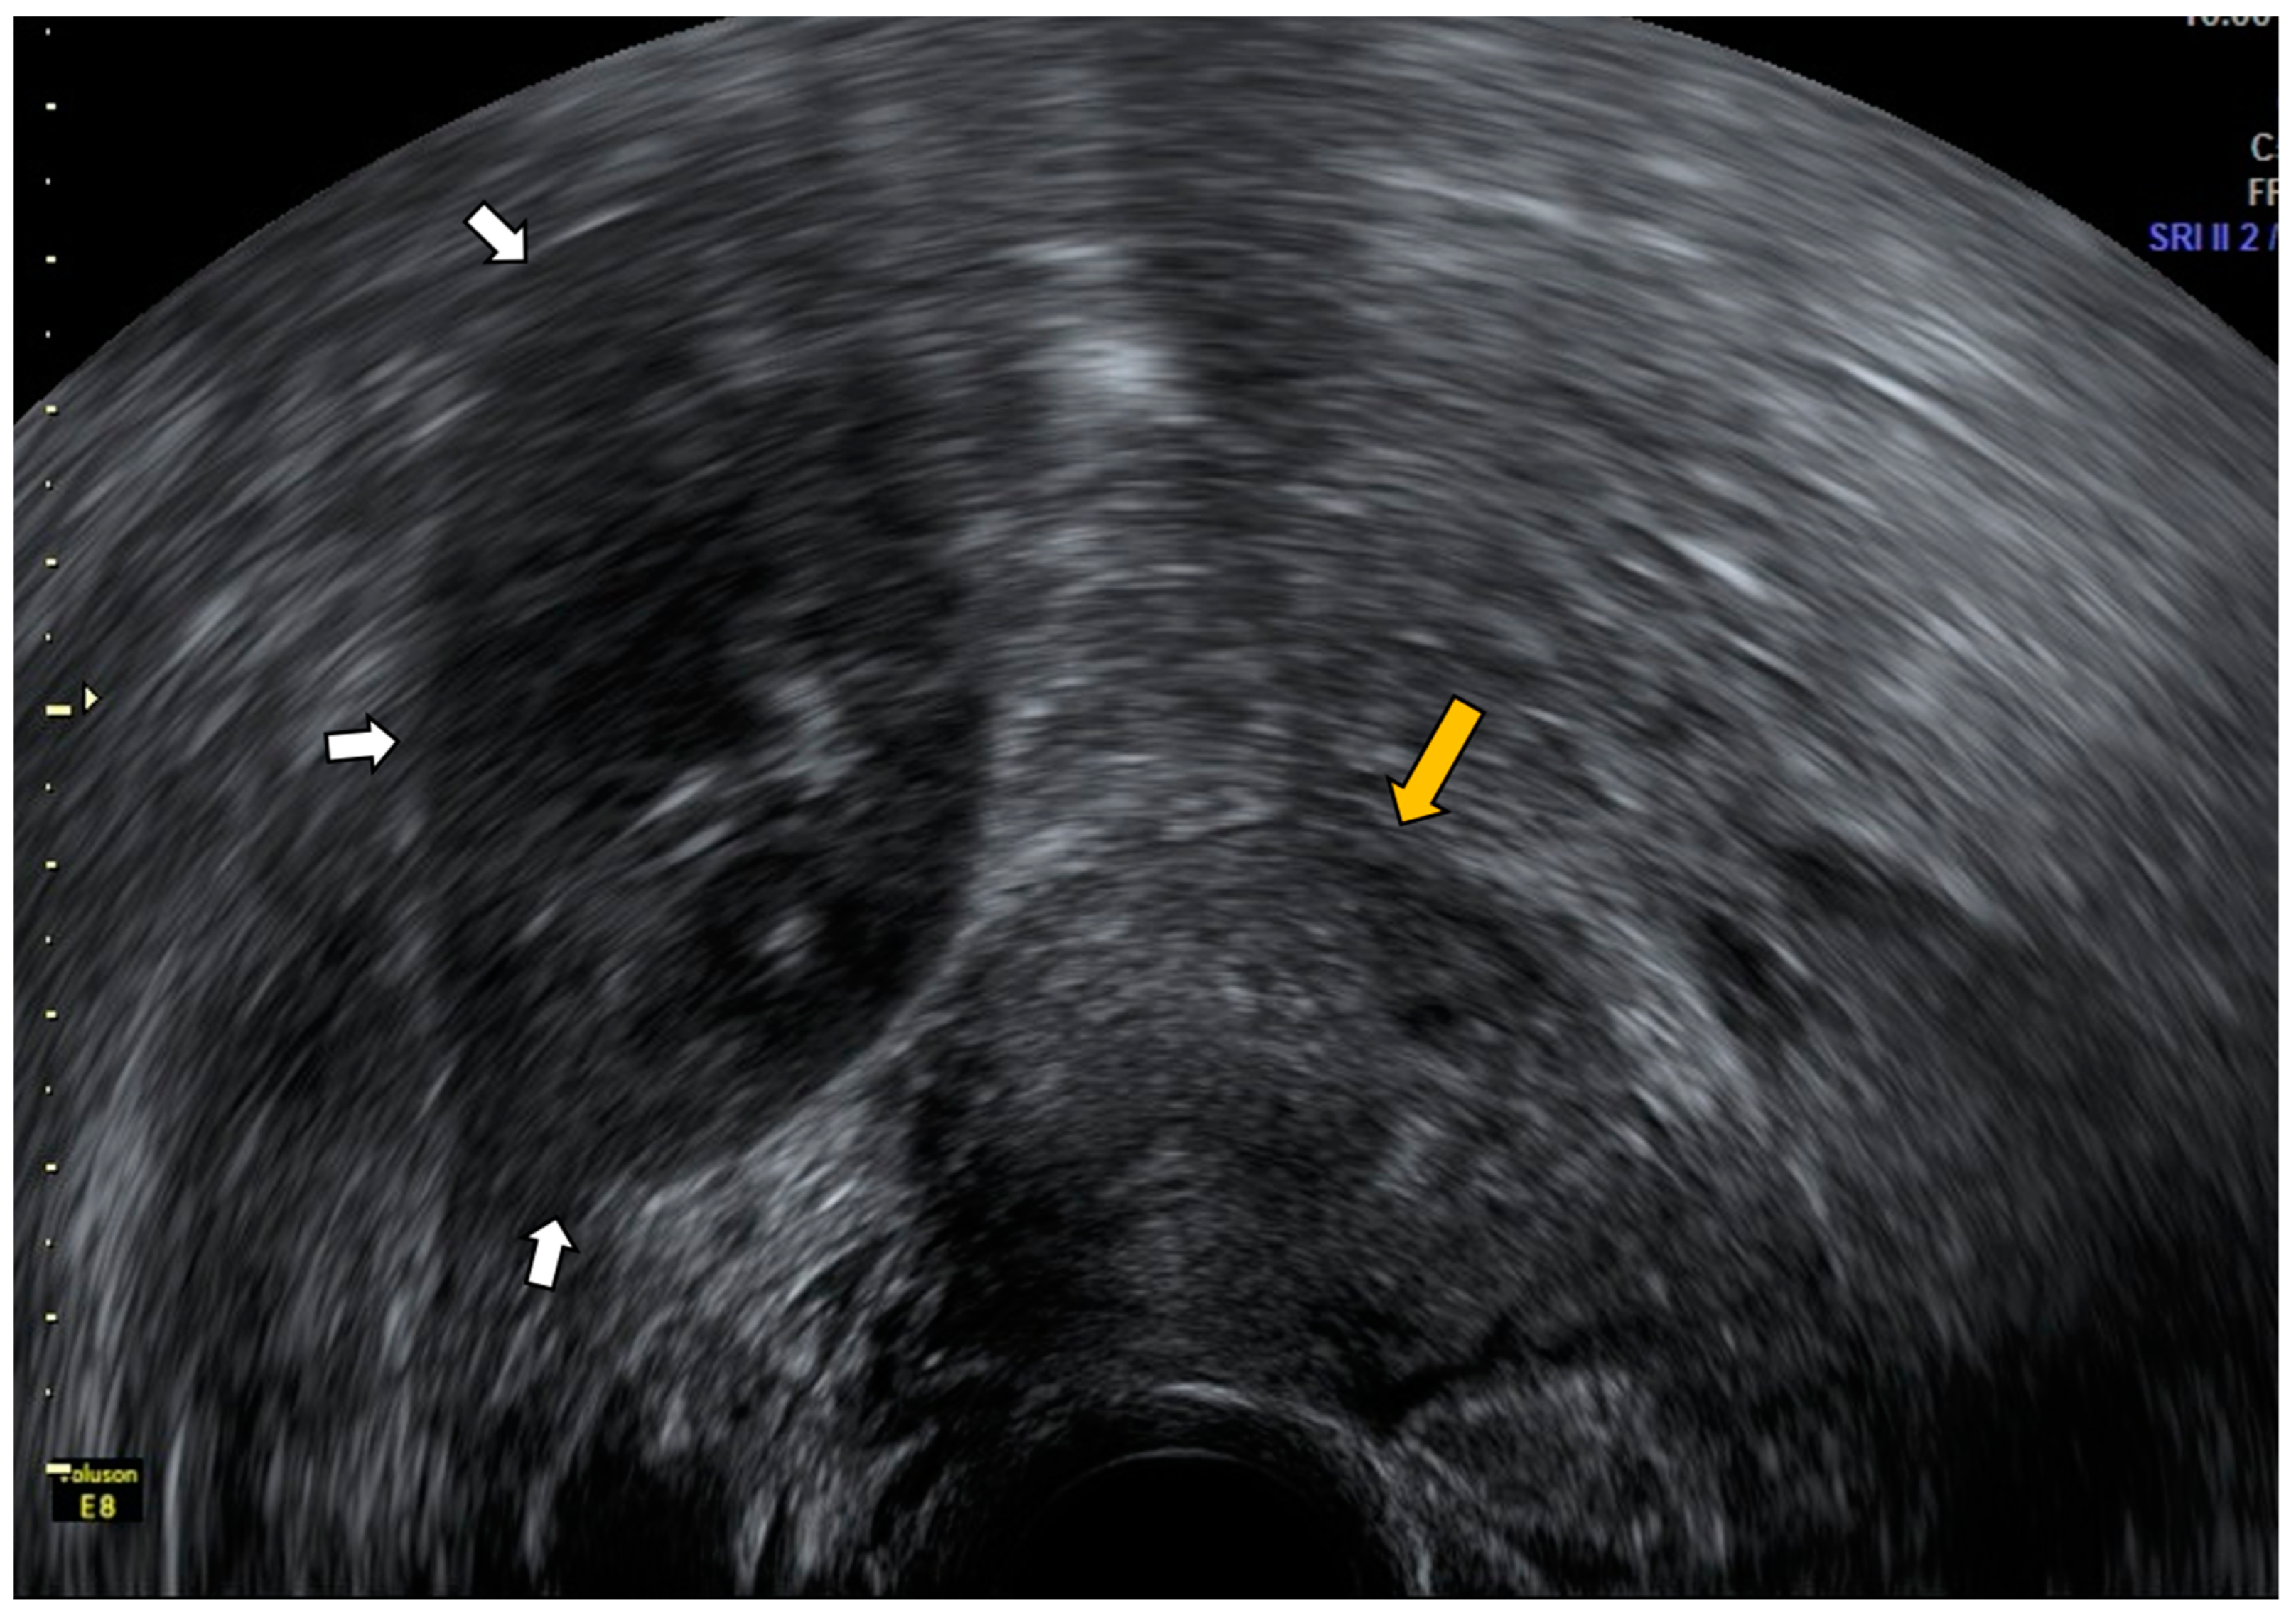

4.1. Pelvic Congestion